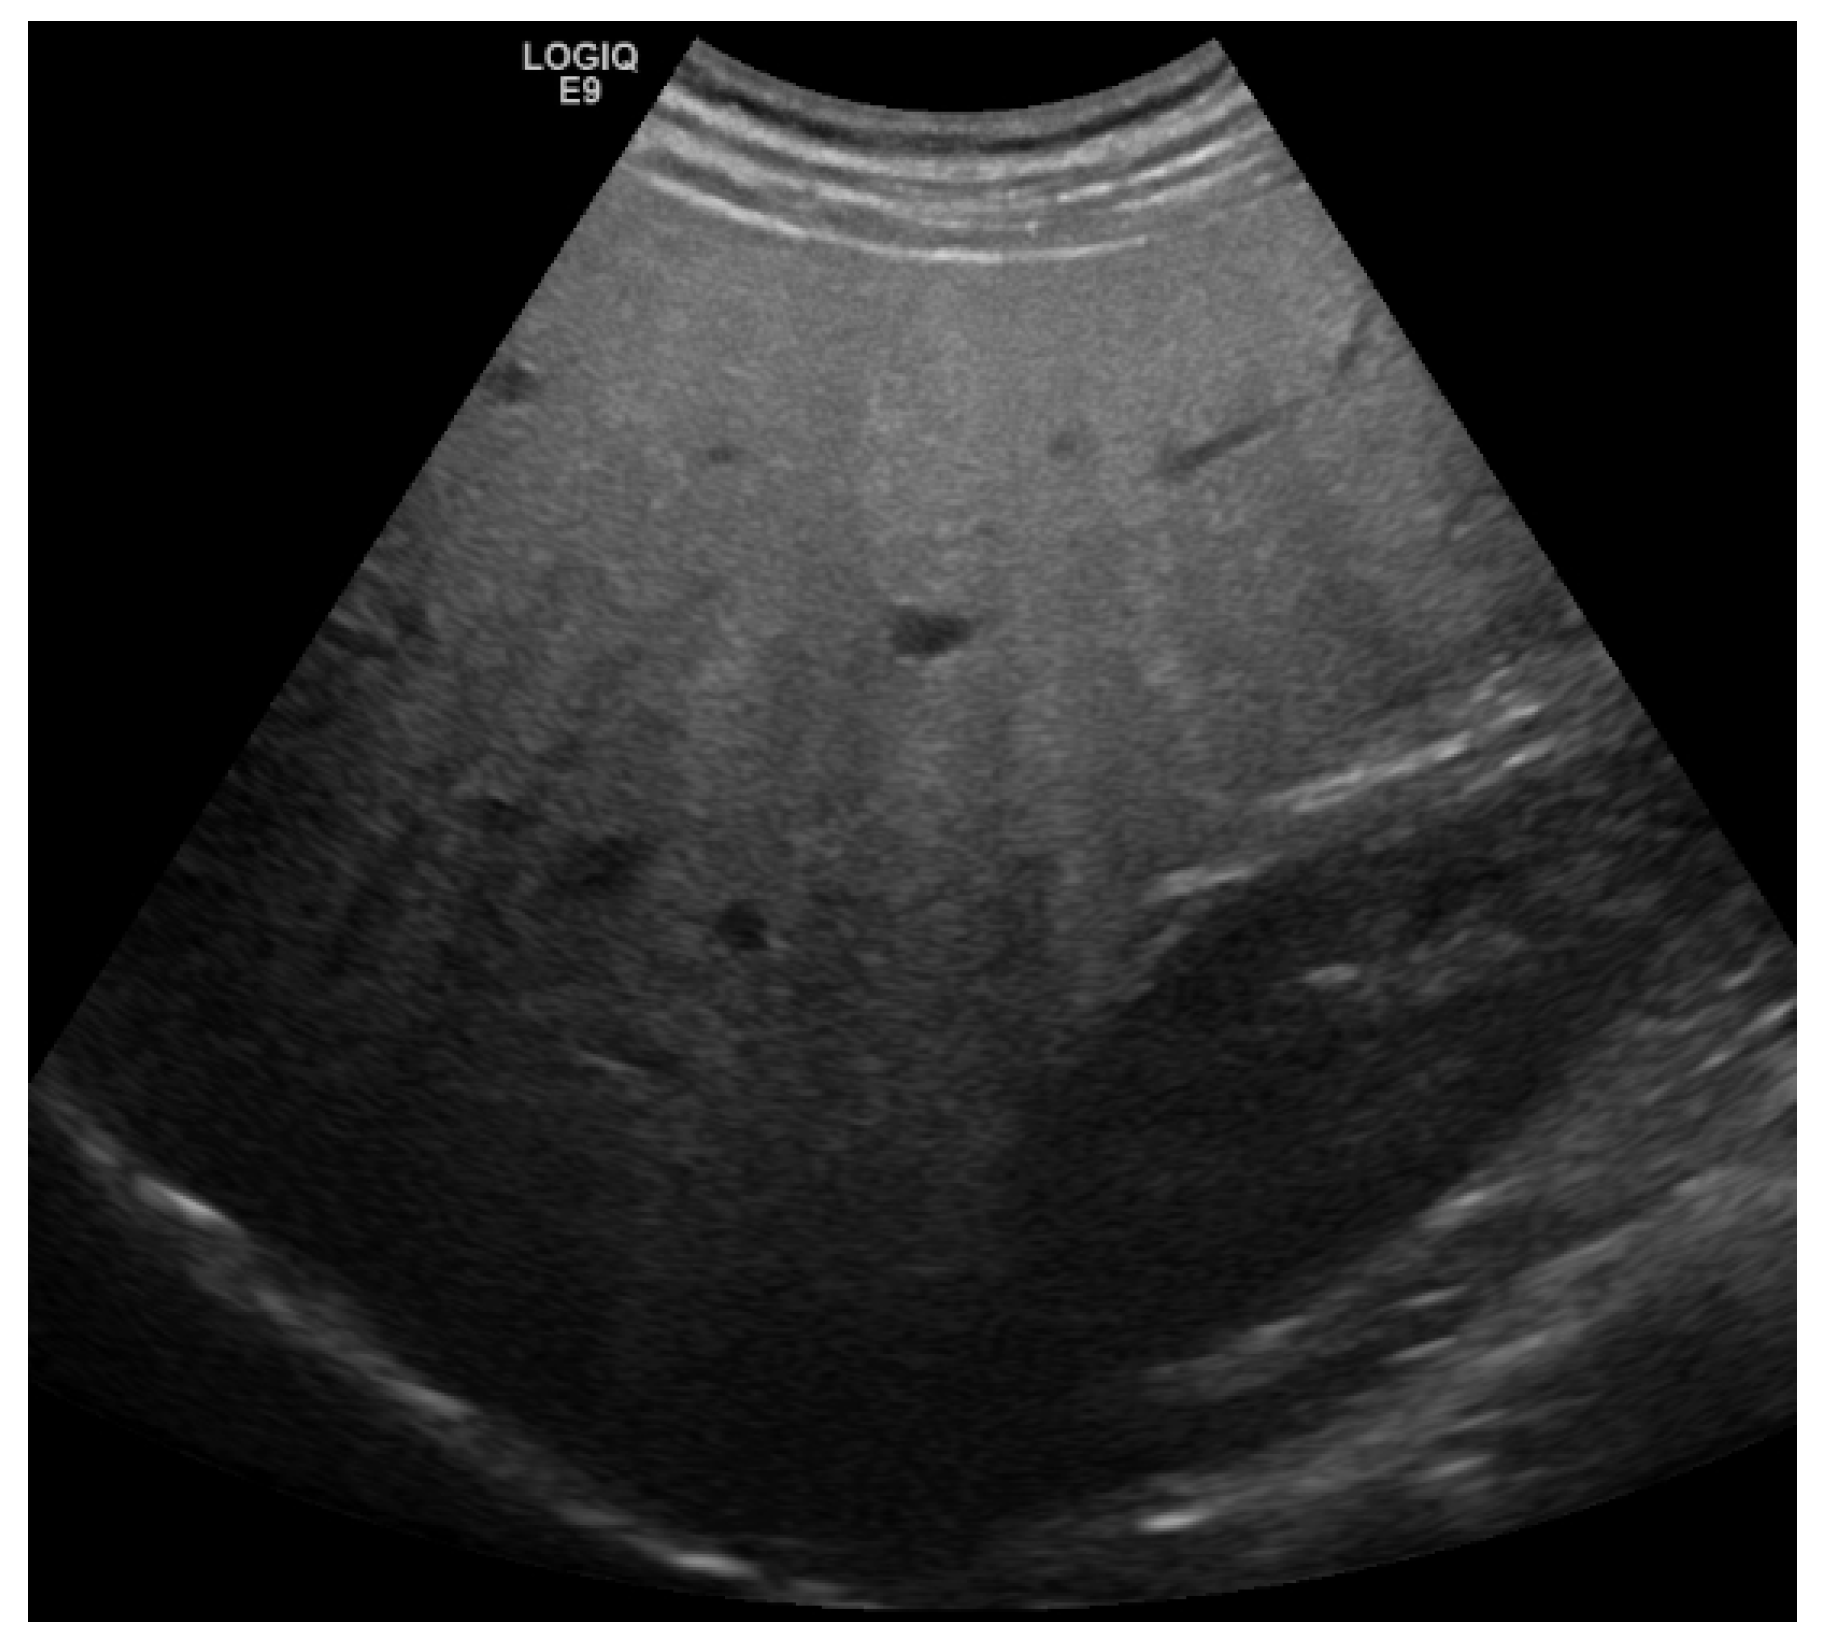

2. Detection and Graduation of Hepatic Steatosis

| B-Mode US [14,15,16,17,18] | 53–76% | 76–93% | -High availability -high-end-device not required | -semiquantitative -low sensitivity for mild steatosis (<30%) |